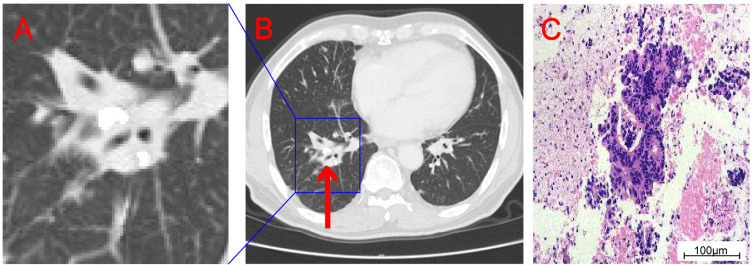

Envafolimab is a novel inhibitor for programmed cell death protein-ligand 1 (PD-L1) that can be administered subcutaneously. It has been found to be effective and safe in the treatment of advanced high microsatellite unstable (MSI-H) / mismatch repair deficient (dMMR) solid tumors. Currently, the efficacy of programmed cell death protein-1 (PD-1) / programmed cell death protein-ligand 1 (PD-L1) inhibitors in the treatment of microsatellite stable (MSS) tumors is not clear. We report a case of advanced colon cancer with MSS metastases in bilateral clavicle, mediastinum, retroperitoneum, bilateral hilum, and left side of thoracic 11/12 vertebral body. After 8 months of Envafolimab treatment, there was a significant reduction in metastatic lesions. As of February 1st, 2024, the patient exhibited no significant adverse reactions. The current efficacy evaluation was the partial response (PR), and the overall survival (OS) was more than 12 months. Considering the safety and efficacy of Envafolimab observed in our case, we believe that Envafolimab may be a promising drug for the treatment of MSS metastatic colon cancer.

Abstract Image